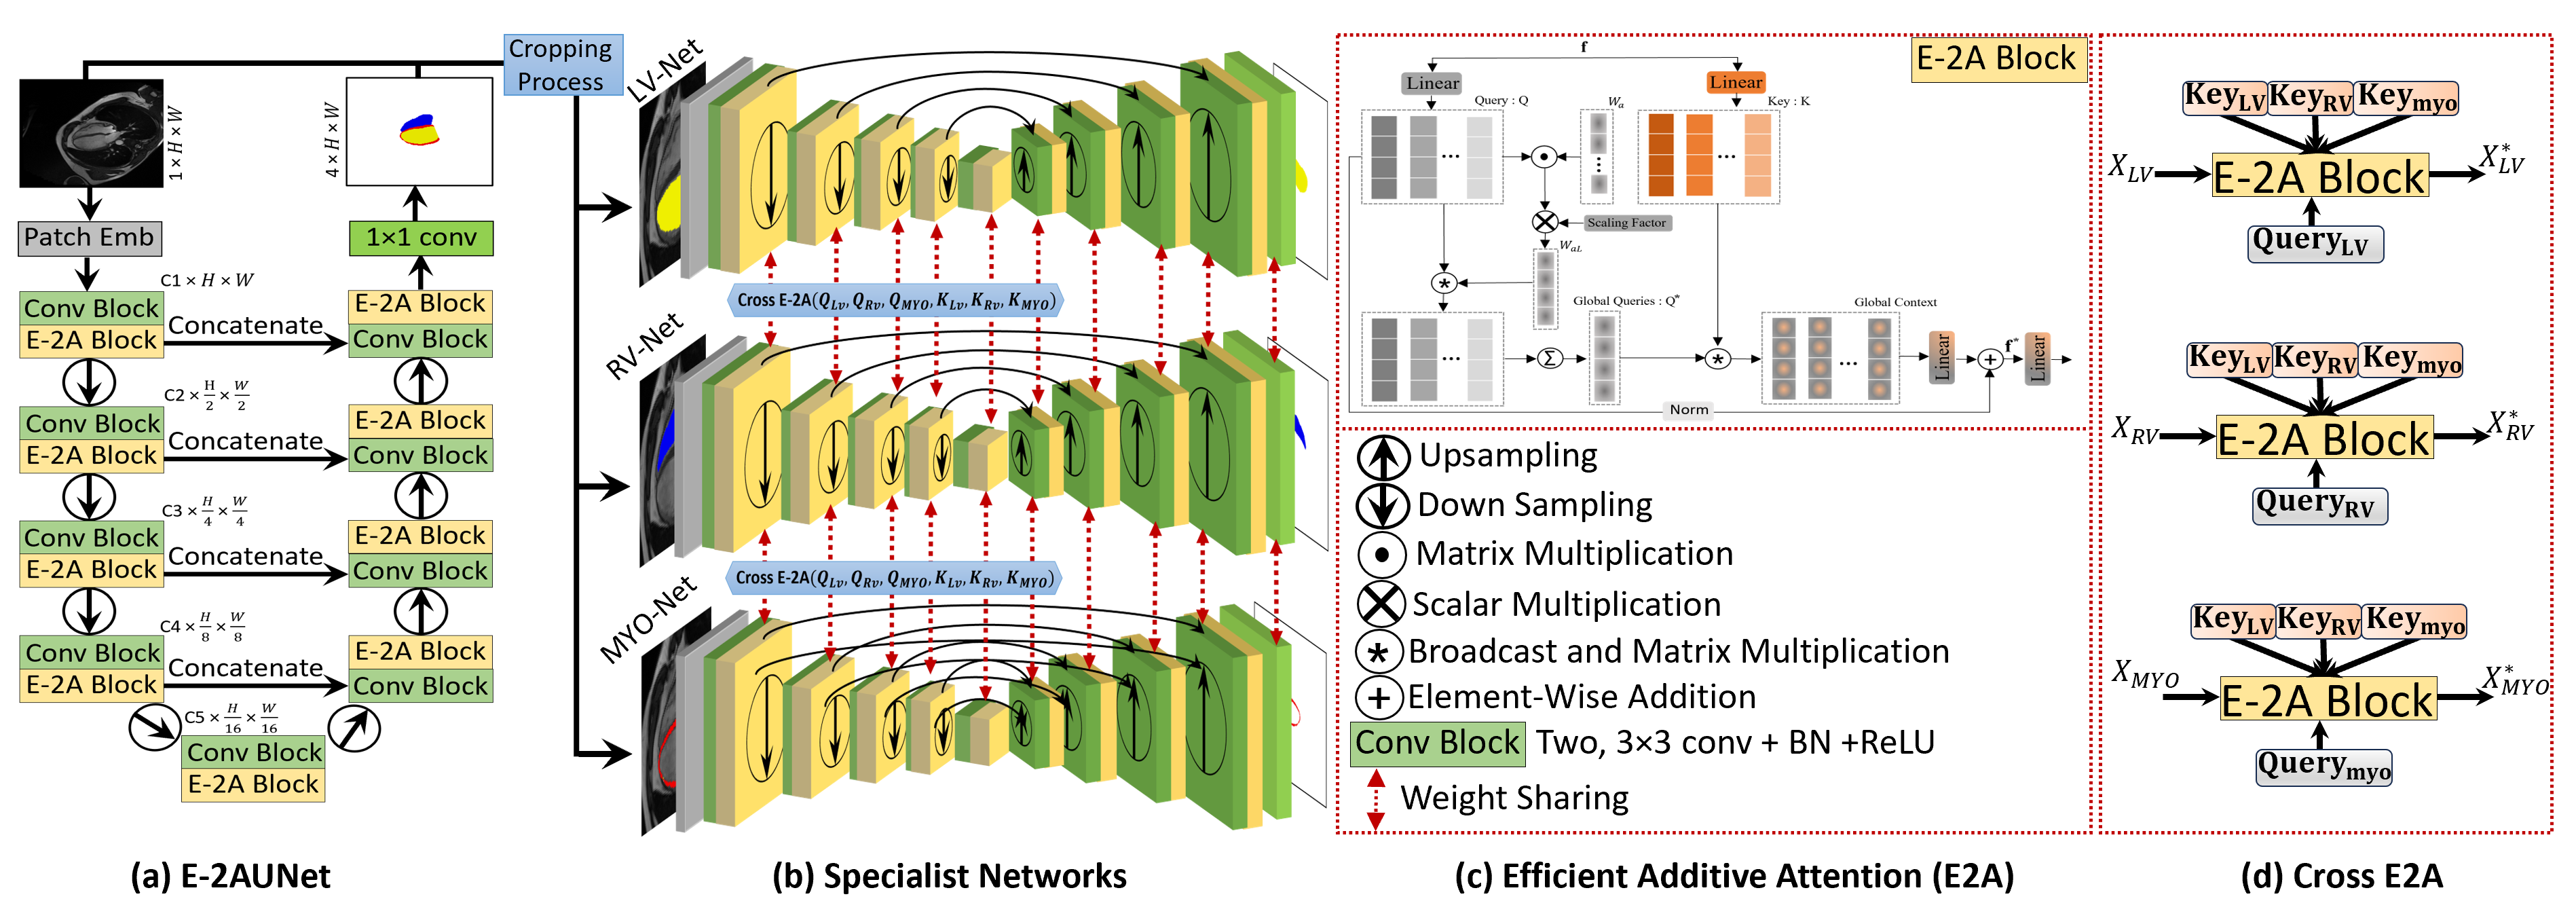

Our proposed approach, CroCNet, implements a two-stage method, shown in Fig. 1, E-2AUNet and specialist networks.

3.1 E-2AUNet

The segmentation network employed in the first stage of CroCNet is the E-2AUNet, depicted in Fig. 1(a). For an input image of size 1HW, the patch embedding layer produces C1 feature maps followed by a convolution block, consisting of two consecutive 33 convolutions with ReLU and batch normalization. The E-2A block is then utilized to capture global information, with this process iterated four times. E-2AUNet can efficiently capture both local and global contexts using convolutional and E-2A blocks. Between the two stages, a downsampling layer reduces spatial dimensions and doubles the channel dimension. The number of feature maps at each stage is increased as C1:32 C2:64 C3:128 C4:256 C5:512. On the decoder side, the convolution block and E-2A block pattern are repeated four times, and an upsampling layer decreases channel numbers while enlarging spatial features. Skip connections are incorporated from the encoder to the decoder for improved gradient flow and connectivity between feature maps. The final segmentation map, representing LV, RV, MYO, and background, is generated using a 11 convolution layer with four kernels and sigmoid activation.

3.2 Efficient-Additive Attention

The E-2A serves as a fundamental component of the proposed E-2AUNet, illustrated in Fig. 1(c). This building block addresses computational inefficiencies associated with self-attention by replacing quadratic complexity with element-wise operations [9], thereby eliminating the need for key-value interactions. The feature matrix (f) is projected into a query (Q) and key (K). The parameter vector is then applied to the query matrix, producing learnable attention weights , followed by a scaling operation. Subsequently, these weights are multiplied by the original query matrix, resulting in a global attention query vector and summation to get a single global query .

| (1) |

The global context is established through the interaction of the key matrix with the global query. A linear transformation layer is employed for the global context to capture query-key interactions and hidden token representations.

| (2) |

3.3 Second Stage Specialist Networks

CroCNet’s second stage consists of specialist networks and cropping, as depicted in Fig. 1(b). Serving as a refinement step, this stage aims to rectify any inaccuracies present in the predictions made during the first stage. We provide details of each component in this stage below.

Cropping: The prediction generated in the first stage utilizes a full-size image, potentially leading to outliers or errors, as illustrated in Fig. 2. To address this, we employ background predictions to identify and remove such outliers. The heart region is extracted from both the intensity image and ground truth. The detection is performed by identifying the largest connected region from element-wise negation of the background predictions. To ensure a safety margin that encompasses the entire heart, the bounding box is expanded by ’shift’ of 15 pixels.

Specialist Networks: The specialist networks, lightweight encoder-decoder networks with a similar architecture to E-2AUNet, have three instances (LV-Net, RV-Net, and MYO-Net) with a weight-sharing strategy and cross-efficient additive attention blocks (cross-E-2A), in the encoders. The specialist networks work only on the cropped heart regions, having a smaller size compared to the original size image. The baseline feature maps start at C1:16 and grow as C2:32 C3:64 C4:128 C4:256. Additionally, the specialist networks share weights at all stages of the encoder-decoder. Interactions between features from the three encoders occur through the cross E-2A block. This cross-attention mechanism serves as a soft relative shape prior, aiding the network in rectifying geometric shapes in different areas of interest and thereby contributing to a more precise segmentation, as discussed in the ablation study.